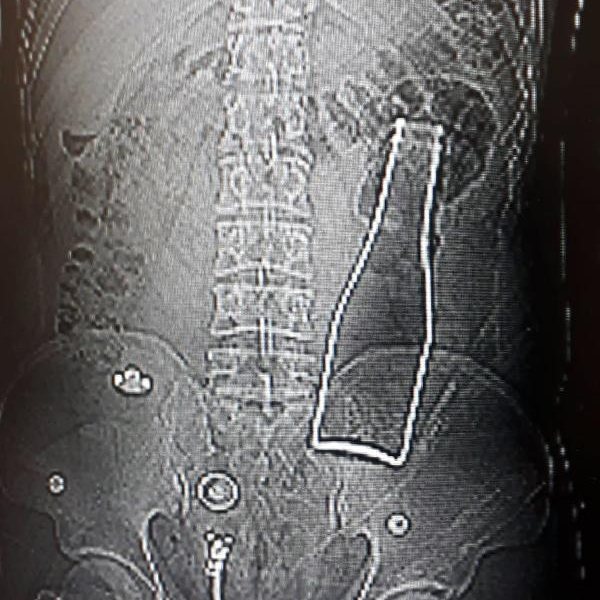

Karaman'da karın ağrısı şikayetiyle hastaneye giden Afganistan uyruklu A.E. adlı erkeğin çekilen röntgen filminde, kalın bağırsağında şişe olduğu ortaya çıktı.

Çekilen röntgen filminde, A.E.'nin kalın bağırsağının bulunduğu bölgede şişe olduğu tespit edildi.